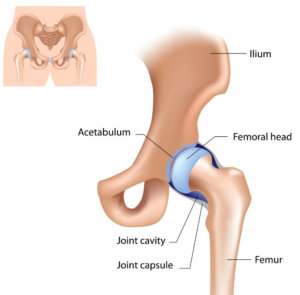

髖關節位於盤骨下端接著大腿骨的位置。這是一個轉動關節,能令我們可以向前、向外、向內、向後提腿。 大腿骨的頂部及盤骨內有一個軟骨組織來幫助減少承托身體的壓力和大腿活動的磿擦。髖關節外層有不同 韌帶及肌肉互相鞏固及承托髖關節活動及重量。( 圖ー至圖三)